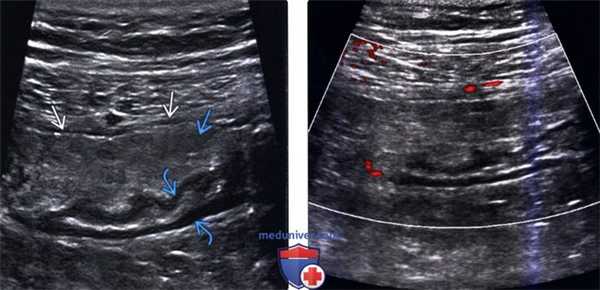

4. УЗИ при сегментарном инфаркте сальника:

• Серошкальное исследование:

о Несжимаемое очаговое эхогенное уплотнение жировой клетчатки, напоминающее объемное образование, лежащее непосредственно под брюшной стенкой в зоне максимальной болезненности

о При допплерографии видно, что в объемном образовании отсутствует сосудистая сеть:

- Может наблюдаться периферическая гиперемия

о В ткани гиперэхогенного объемного образования определяются узловые или линейные гипоэхогенные бессосудистые зоны с нечеткими контурами

(Левый) При УЗИ в черно-белом режиме определяется четко отграниченное эхогенное образование с гипоэхогенным ободком утолщенной висцеральной брюшины и нечеткими гипоэхоген-ными очагами в центре. Обратите внимание на отсутствие изменений гипоэхогенных слоев, представляющих собой собственную мышечную оболочку сигмовидной кишки.

(Правый) При цветовой допплерографии отмечается отсутствие сосудистой сети образования.